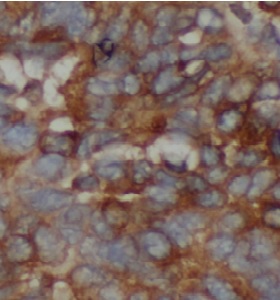

| 验证图片 | Immunohistochemical analysis of paraffin-embedded human liver cancer tissue slide using FNab10115( TRAF2 Antibody) at dilution of 1:200 HeLa cells were subjected to SDS PAGE followed by western blot with FNab10115 (TRAF2 antibody) at dilution of 1:1000 |